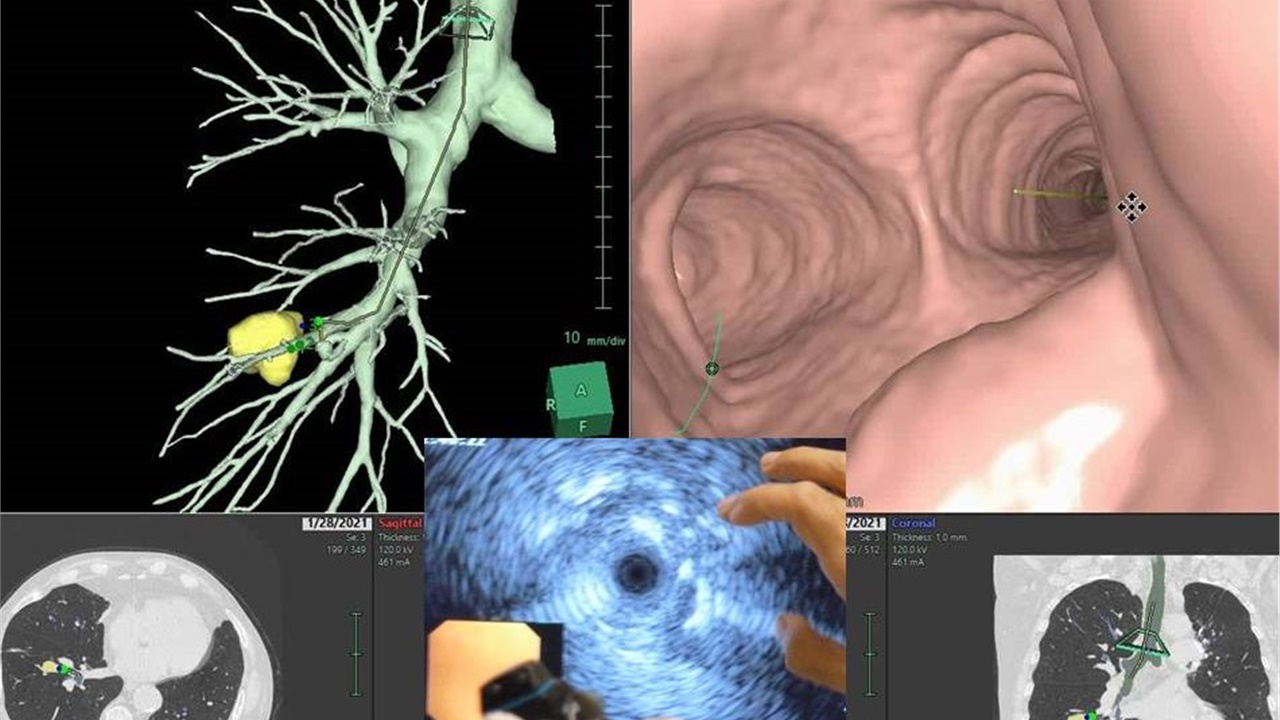

Bronchoscopy On Air #1: Peripheral Pulmonary Lesion / Rebiopsy